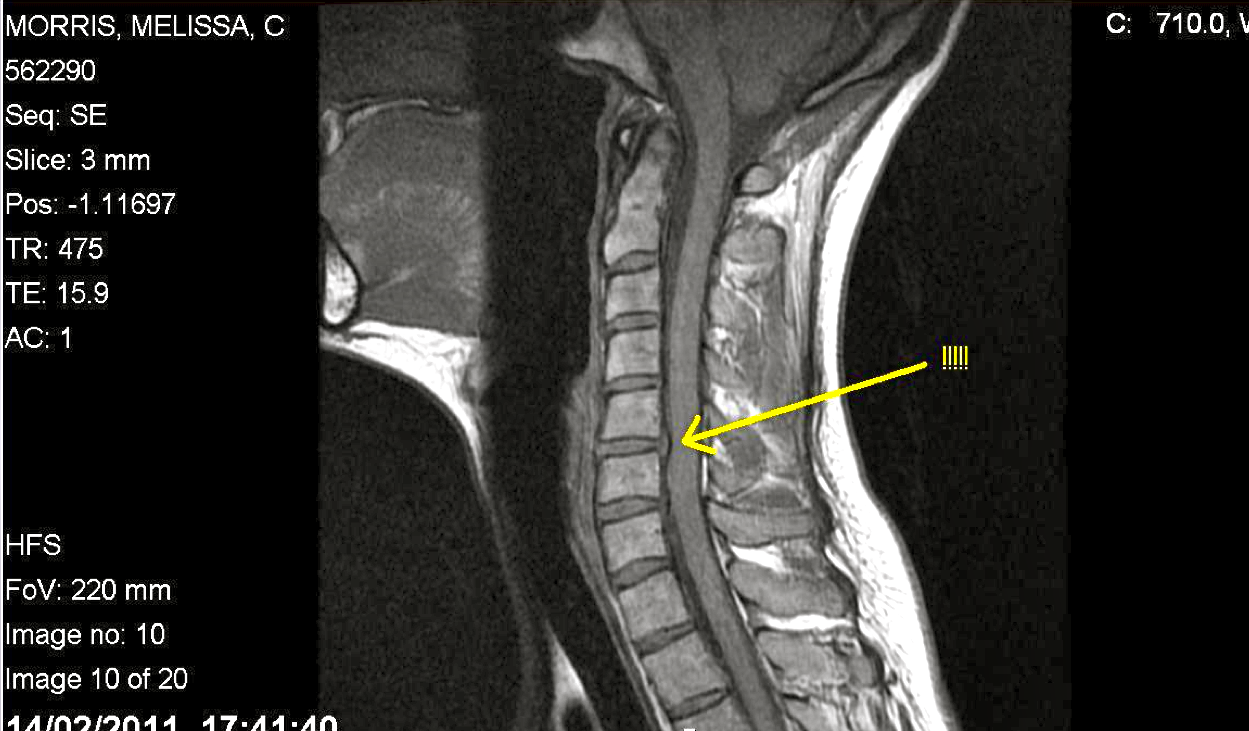

IMAGES IN EMERGENCY MEDICINE

Then the injury was repaired surgical treatment.3,4 Images in Emergency Medicine Sonoo et al. Title: Child With Acute Neck Pain Author: Tomohiro Sonoo MD Subject: Annals of Emergency Medicine, 68 (2016) 5-6. doi:10.1016/j.annemergmed.2015.12.005 ... Get Content Here